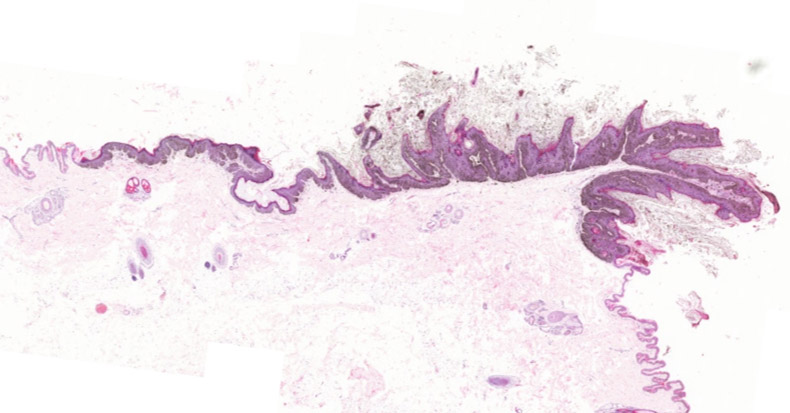

Microscopic examination of haired skin sections revealed a well-demarcated area of marked papillomatous epidermal hyperplasia and moderate hyperkeratosis, consisting of both orthokeratotic and parakeratotic forms. The epidermis showed hypergranulosis with enlarged keratohyalin granules, and keratinocytes exhibited koilocytosis with swollen pale cytoplasm and perinuclear clearing. There was prominent melanin deposition within all epidermal layers and a few melanophages in the superficial dermis. The underlying dermis contained minimal perivascular lymphoplasmacytic infiltrate without significant fibroplasia, ulceration, or other abnormalities.

The diagnosis was pigmented viral plaque of the ventral abdominal skin.